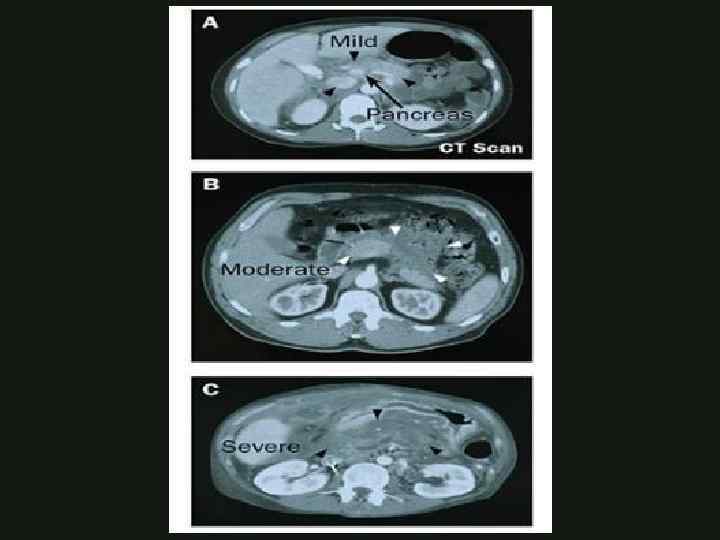

КОМПЬЮТЕРНАЯ ТОМОГРАФИЯ Позволяет оценить объём поражения поджелудочной железы Выявляет степень некроза поджелудочной железы Позволяет прогнозировать течение болезни КАФЕДРА ХИРУРГИИ МОСКОВСКОГО ФАКУЛЬТЕТА

КОМПЬЮТЕРНАЯ ТОМОГРАФИЯ Позволяет оценить объём поражения поджелудочной железы Выявляет степень некроза поджелудочной железы Позволяет прогнозировать течение болезни КАФЕДРА ХИРУРГИИ МОСКОВСКОГО ФАКУЛЬТЕТА

КОМПЬЮТЕРНАЯ ТОМОГРАФИЯ • А. Нормальные размеры и контрастирование железы • B. Увеличение в размерах • C. Перипанкреатит с воспалительными изменениями жировой ткани • D. С + наличие жидкости в переднем параренальном пространстве • E. D + наличие жидкости в сальниковой сумке Balthazar КАФЕДРА ХИРУРГИИ МОСКОВСКОГО ФАКУЛЬТЕТА

КОМПЬЮТЕРНАЯ ТОМОГРАФИЯ • А. Нормальные размеры и контрастирование железы • B. Увеличение в размерах • C. Перипанкреатит с воспалительными изменениями жировой ткани • D. С + наличие жидкости в переднем параренальном пространстве • E. D + наличие жидкости в сальниковой сумке Balthazar КАФЕДРА ХИРУРГИИ МОСКОВСКОГО ФАКУЛЬТЕТА

КОМПЬЮТЕРНАЯ ТОМОГРАФИЯ • А=0 • В=1 • С=2 • D=3 • Е=4 • Отсутствие некроза=0 • Некроз до 13 поджелудочной железы=2 • Некроз 50% поджелудочной железы=4 • Некроз >50% поджелудочной железы=6 КАФЕДРА ХИРУРГИИ МОСКОВСКОГО ФАКУЛЬТЕТА

КОМПЬЮТЕРНАЯ ТОМОГРАФИЯ • А=0 • В=1 • С=2 • D=3 • Е=4 • Отсутствие некроза=0 • Некроз до 13 поджелудочной железы=2 • Некроз 50% поджелудочной железы=4 • Некроз >50% поджелудочной железы=6 КАФЕДРА ХИРУРГИИ МОСКОВСКОГО ФАКУЛЬТЕТА

КОМПЬЮТЕРНАЯ ТОМОГРАФИЯ • 1 -2 балла – вероятность тяжелого панкреатита тяжелыми осложнениями невозможна • 3 -6 баллов – вероятность тяжелого панкреатита с тяжелыми осложнениями мала • 7 -10 баллов – вероятность тяжелого панкреатита с тяжелыми осложнениями 92%, летальность – 17% КАФЕДРА ХИРУРГИИ МОСКОВСКОГО ФАКУЛЬТЕТА

КОМПЬЮТЕРНАЯ ТОМОГРАФИЯ • 1 -2 балла – вероятность тяжелого панкреатита тяжелыми осложнениями невозможна • 3 -6 баллов – вероятность тяжелого панкреатита с тяжелыми осложнениями мала • 7 -10 баллов – вероятность тяжелого панкреатита с тяжелыми осложнениями 92%, летальность – 17% КАФЕДРА ХИРУРГИИ МОСКОВСКОГО ФАКУЛЬТЕТА